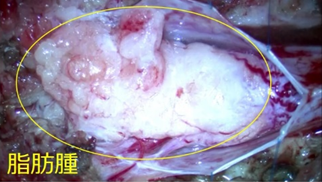

脊髄脂肪腫は、脊髄が形成される過程で脂肪組織が入り込んでくることが原因で生じます。皮下脂肪が脊髄までつながって脊髄を圧迫し、さらに脊髄が脂肪腫によって牽引され脊髄係留という状態になります。全く無症状のこともありますし、下肢の麻痺や排尿排便障害などの症状がすでに出ていることもあります。脂肪“腫”という病名ですが、“腫瘍”ではなくあくまでも脂肪の塊です。大きくなったり転移することはありません。

無症状の場合に手術を行うかは年齢や難易度によって個々に判断することになりますが、すでに症状がある場合には通常手術を行います。手術の目的は、無症状の場合は将来症状が出てくるのを防ぐことであり、すでに症状が出ている場合はこれ以上悪化するのを防ぐことです。

脂肪腫の付近には重要な神経が多数走行しています。当科の手術では、これらを1本も損傷しないように膀胱・直腸・下肢の神経モニタリングを併用して安全に脂肪腫の摘出を行なっています。